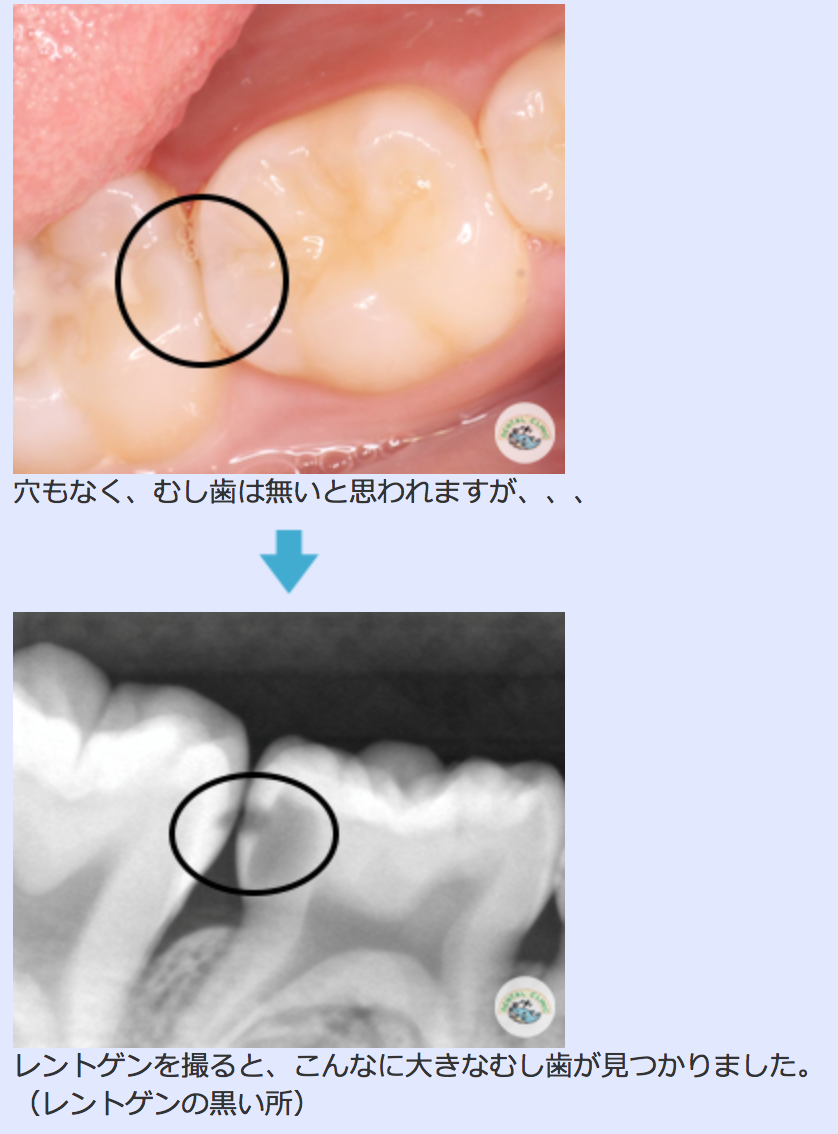

今までは、文章のみの「Q and A」でしたが、今回いくつかの質問の部分に写真を掲載させて頂きました。やはり百聞は一見に如かずと言いますので、写真を見ていただいたほうが、より理解していただけると考えています。

むし歯についての写真の一部→

写真掲載については全て掲載した写真の患者様に承諾をいただき、承諾書に署名をいただいています。ご協力有難うございました。